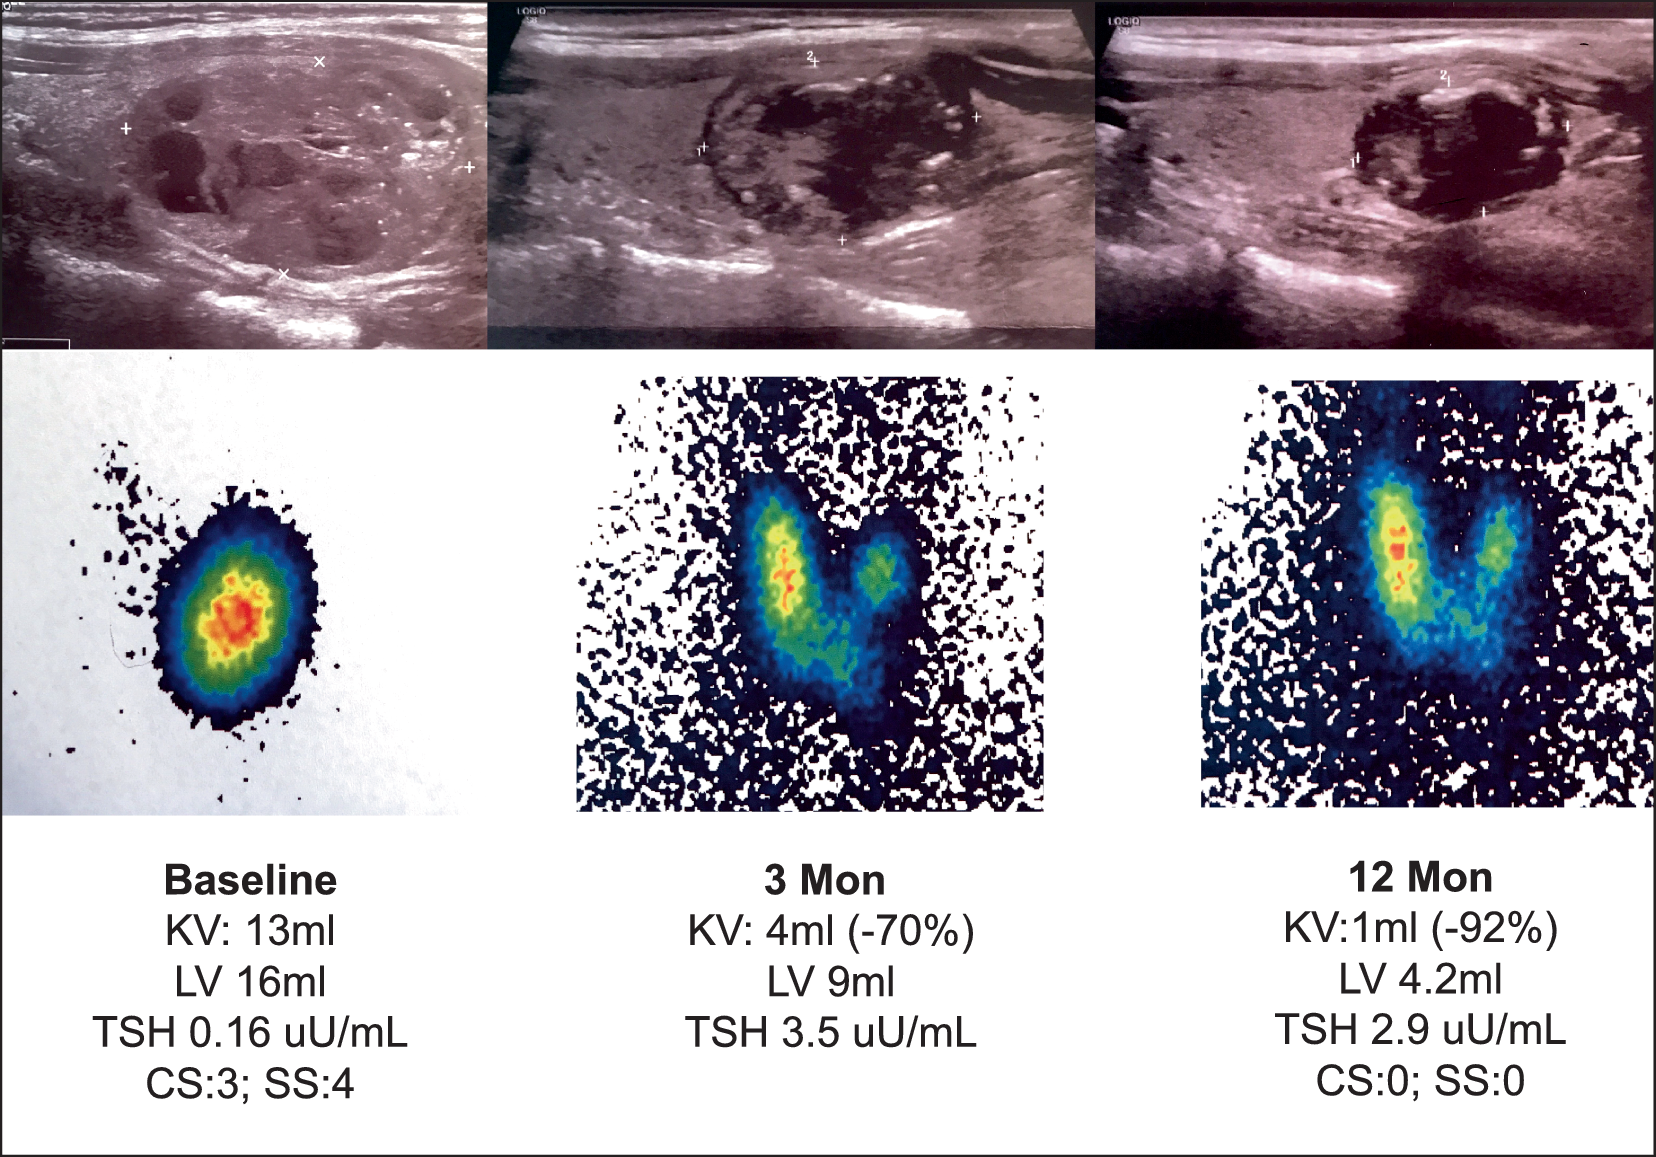

Abb. 3

Beispiel einer Radiofrequenzablation (RFA) eines autonomen Adenoms. 48-jährige Patientin, autonomes Adenom seit Jahren bekannt, zuletzt deutliches Wachstum und Entwicklung einer latenten Hyperthyreose. Operation wurde empfohlen. Der Ausgangsbefund ist ein 13 ml großes, 40 % zystisches, autonomes Adenom, welches den Großteil des linken Schilddrüsenlappens einnimmt, funktionell dekompensiert. Die Ultraschallbilder zeigen den Sagittalschnitt durch den linken Schilddrüsenlappen mit den morphologischen Veränderungen 3 und 12 Monate nach der RFA. Da das behandelte autonome Adenom nach der RFA bindegewebig umgebaut wird, wird aus dem in der Technetium-99m-Szintigraphie vormals „heißen“ Knoten ein „warmer“ oder idealerweise sogar ein „kalter“ Knoten. KV Knotenvolumen, LV Lappenvolumen, CS visueller Knotenscore (bis Grad 3); SS Symptomatikscore (bis Grad 10)